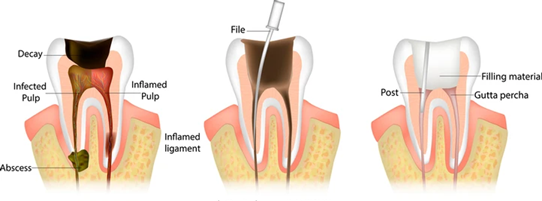

Are you dealing with constant tooth pain, sensitivity to hot or cold, or swelling around a tooth? These symptoms can make everyday activities like eating and speaking uncomfortable. In many cases, the underlying cause is an infection deep inside the tooth. A root canal offers a reliable way to remove the infection and preserve the natural tooth, helping restore both comfort and function. With modern techniques, a painless root canal is now possible, making the treatment far more comfortable than commonly perceived.

At The Smile Connect, a premium dental clinic in Kandivali, every procedure is carefully planned under the expert guidance of Dr. Uttkarsh Shah to ensure effective removal of infection and preservation of the natural tooth.

3. Removal of Infection

4. Shaping and Disinfection

5. Filling and Sealing

Once cleaned, the canals are filled with a biocompatible material and sealed. A temporary tooth filling may be placed between sittings until the final restoration is complete.

6. Final Restoration with Crown